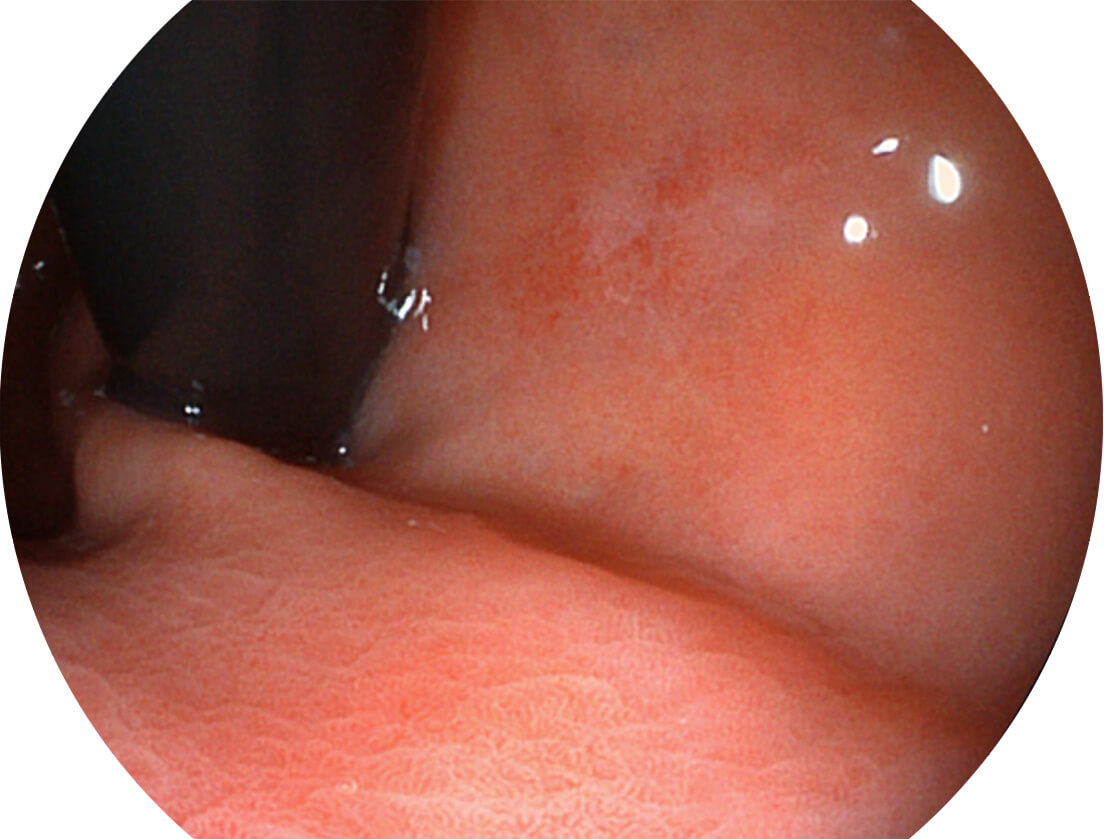

Versatile Intelligent Staining Technology, VIST

强调浅层黏膜结构的同时,保证照明亮度和提升浅层微血管与中层血管颜色对比度,病变边界更清晰。

白光图像